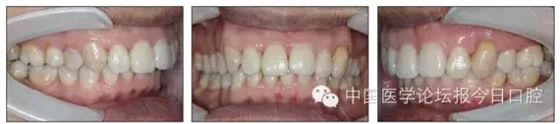

本病例為慢性牙周炎致前牙漂移、深覆(牙合)患者。本病例采用無托槽隱形矯治技術(shù)進行治療。無托槽隱形矯治器具有可摘戴、便于口腔衛(wèi)生維護和牙周治療的優(yōu)點,更適合于伴有牙周炎的錯(牙合)畸形患者的治療。 患者男,48歲,前牙有縫、前突求診。 患者面部對稱,側(cè)面觀上頜前突,下頜后縮。 口內(nèi)情況:恒牙列,24、34、44缺失,磨牙Ⅲ類關(guān)系,上牙列散隙,上前牙扇形漂移。前牙深覆(牙合)、深覆蓋??谇恍l(wèi)生較差,11與12間牙齦乳頭紅腫,多個牙探診有牙周袋形成,11松動Ⅰ度,余切牙松動(-),患者面像及口內(nèi)像如圖1、2所示。 圖1 治療前面像 圖2 治療前口內(nèi)像 全口曲面體層片(圖3)顯示,患者全牙列牙槽骨吸收;根尖片(圖4)示11近中牙槽骨角形吸收已達根尖1/3,21牙槽骨嵴頂吸收至根1/2,23牙槽骨近中骨板角形吸收至根1/2。磨牙區(qū)骨嵴頂吸收3mm。治療前頭顱側(cè)位片見圖3,治療前ODS模型見圖5。 圖4 治療前根尖片 圖5 治療前ODS模型 牙型:安氏Ⅲ類。骨型:Ⅱ類。面型:上頜前突,下頜后縮。 問題列表為:①上牙列間隙;②上切牙病理性牙移位;③前牙深覆(牙合)、深覆蓋;④24、34、44缺失;⑤慢性牙周炎。 矯治目標包括:①排齊牙列,關(guān)閉牙列間隙;②改善前牙深覆(牙合)、深覆蓋;③改善牙周狀況。 矯治設(shè)計有:①牙周基礎(chǔ)治療與維護。②壓低、內(nèi)收上切牙,關(guān)閉上牙列間隙。③壓低下切牙,伸長下后牙,整平Spee曲線,改善前牙覆(牙合)、覆蓋。 患者進行全口齦上潔治、齦下刮治,口腔衛(wèi)生宣教,并按牙周醫(yī)師的要求,每2~3個月行牙周檢查與治療。 牙周基礎(chǔ)治療結(jié)束3個月,開始隱形矯治。于14、25、35、36、45、46上粘接附件(圖6),于16、26(牙合)面粘接(牙合)墊。 圖6 ODS設(shè)計附件粘接圖示 矯治過程中注意(牙合)墊是否脫落或磨損,及時修補。 注意上前牙內(nèi)收時有無咬合干擾,及時調(diào)(牙合)。下頜前磨牙伸長到位后,磨除16、26(牙合)墊。 下頜佩戴第24步矯治器時,分別在36、37、46、47的頰、舌側(cè)粘接舌扣,矯治器上預(yù)留伸長空間,用3/16英寸、3.5盎司皮圈牽引,輔助伸長下磨牙(圖7)。 患者共戴用矯治器上頜32步,下頜26步。 矯治后,牙列間隙關(guān)閉,面型及覆(牙合)覆蓋改善。11根尖片(圖8)顯示,治療后較治療前,牙周支持組織增加,牙槽骨角形吸收區(qū)水平向縮小0.3mm,垂直向縮小0.6mm。11松動Ⅰ度,余切牙無松動。 圖8 治療后根尖片 圖9 治療后口內(nèi)像 圖10 治療后X線檢查 圖11 治療后ODS模型 正畸-牙周聯(lián)合治療對于牙周組織的影響 多學(xué)科綜合治療牙周炎患者不再是正畸治療的禁忌證。良好的牙周治療為正畸治療中的牙齒移動打下堅實基礎(chǔ),而正畸治療排齊牙齒、去除(牙合)干擾,有利于牙周健康。 牙周炎患者的正畸治療必須在牙周炎癥得到控制后才能進行,否則,菌斑會隨著牙齒的移動,特別是壓低而使牙周炎癥加重。牙周炎的正確診斷、牙周炎癥控制、正畸治療中和治療后的認真維護是治療成功的關(guān)鍵。根據(jù)臨床需要,一般每2~4周做一次潔治,每3個月進行牙周評估,同時患者必須進行非常良好的日??谇恍l(wèi)生維護。 固定矯治器使得牙周檢查、潔治和日??谇恍l(wèi)生維護變得困難,隱形矯治器可自行摘戴,便于患者日常維護和牙周治療,節(jié)約時間,提高菌斑控制效果。 有臨床研究表明,對于存在(牙合)創(chuàng)傷,伴有角形吸收的患牙,經(jīng)過牙周翻瓣手術(shù)控制住牙周炎癥后,使用正畸輕力壓低患牙,可以改善牙槽骨吸收的程度,并獲得一定程度的牙周新附著。本病例切牙壓低后,原來的牙槽骨吸收有改善。 病理性牙移位 病理性牙移位(PTM)在重度牙周炎患者中的發(fā)生率為30%~50%,且常見于上前牙區(qū)。其主要由于牙周支持組織喪失尤其是骨組織的丟失,咬合因素(如后牙缺失、前牙深覆牙合、牙合創(chuàng)傷等),頰舌唇肌力量不平衡及牙周和根尖周組織炎癥所致,是牙周炎患者要求正畸治療的主要原因之一。 PTM須通過正畸、牙周聯(lián)合,有時須配合修復(fù)才能達到理想的治療效果。正畸治療通常是壓低牙齒,臨床研究表明,牙周手術(shù)配合正畸壓低可以產(chǎn)生新附著,有利于PTM牙周組織的恢復(fù)。 本病例右上中切牙牙槽骨角形吸收,在盡量保證治療前后根尖片投照角度一致的情況下,以鄰牙作為校準,在根尖片上對治療前后的骨量進行評價,治療后牙槽骨角形吸收區(qū)水平向縮小0.3 mm,垂直向縮小0.6mm。盡管根尖片并不能說明骨量改變,但從影像學(xué)上能看到骨吸收區(qū)域有所減小。 無托槽隱形矯治器矯治牙周病的優(yōu)勢 無托槽隱形矯治器具有可摘戴、便于口腔衛(wèi)生維護和牙周治療的優(yōu)點,更適合于伴有牙周炎的錯(牙合)患者的治療;同時,無托槽隱形矯治器佩戴后具有牙弓夾板和(牙合)板的作用,可有效減少側(cè)向力,有利于牙周的恢復(fù)和減輕牙齒松動;由于無托槽隱形矯治器的設(shè)計是在三維數(shù)字模型上進行的,每個矯治器移動牙齒的數(shù)量和每個牙齒的移動距離可以得到量化控制,因而可以根據(jù)患者牙槽骨水平和對矯治力的耐受情況個性化設(shè)計矯治力,并且可以根據(jù)矯治中牙齒移動情況調(diào)整后續(xù)矯治器的設(shè)計。 有關(guān)磨牙伸長 單純使用無托槽隱形矯治器同步伸長后牙比較困難。該病例先使用磨牙(牙合)墊打開咬合,通過矯治器伸長前磨牙,在前磨牙建立咬合后,磨除磨牙上的(牙合)墊,通過輔助牽引伸長磨牙,最終達到伸長后牙、整平Spee曲線的目的。 史真,主任醫(yī)師,現(xiàn)任北京黃寺整形外科醫(yī)院口腔科主任,第四軍醫(yī)大學(xué)口腔正畸學(xué)碩士,為世界正畸醫(yī)師聯(lián)盟(WFO)會員、全軍口腔醫(yī)學(xué)專業(yè)委員會委員、中華口腔正畸專業(yè)委員會委員、中華醫(yī)學(xué)美學(xué)與美容學(xué)會齒科美容學(xué)組成員、北京口腔醫(yī)學(xué)會兒童口腔專業(yè)委員會常務(wù)委員、北京口腔醫(yī)學(xué)會正畸專業(yè)委員會委員、《中華醫(yī)學(xué)美學(xué)與美容》雜志審稿專家,是我國最早開展無托槽隱形矯治技術(shù)的口腔醫(yī)師之一。